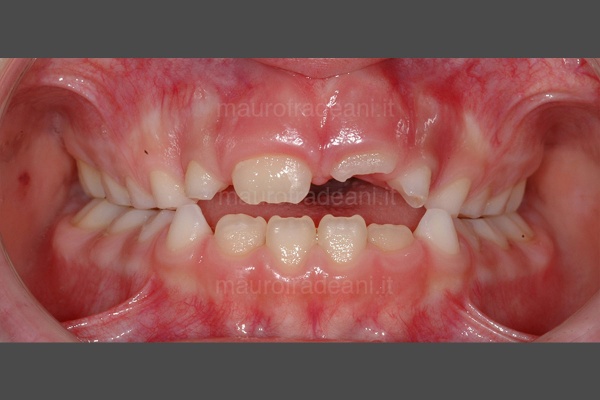

Early orthodontics: malocclusion and tooth crowding

1/6: Initial picture taken before early orthodontic treatment. The young patient presents a first class malocclusion with misalignment and dental crowding in both arches. The upper right central incisor is in reverse bite with the lower one.

2/6: Upper occlusal picture showing the misalignment of the upper central incisors.

3/6: Lower occlusal picture showing the dental crowding on the lower arch.

4/6: The right lateral view shows the backward position of the upper right central incisor, which determines the incorrect occlusion with the lower arch.

5/6: Right lateral view picture showing the correct position of the upper right central incisor at the end of the orthodontic treatment.

6/6: Front view at the end of the orthodontic treatment: both the misalignment and the initial dental crowding have been fixed.